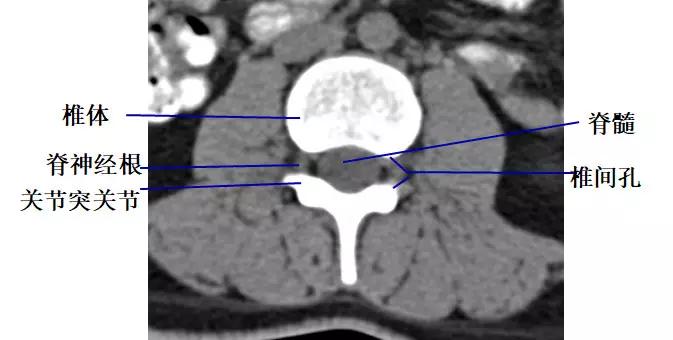

3.椎间孔

位于椎管前外侧,其内的脊神经根呈软组织密度,周围有低密度的脂肪组织环绕。

椎间孔前为椎体,后为椎小关节,上下为椎弓根,内与侧隐窝相连,有脊神经根通过。

侧隐窝:向下外续于椎间孔,有脊神经经过:前壁为椎体后外缘;后壁为上关节突前面与黄韧带;外界为椎弓根。

正常前后径为3-5mm,<3mm侧隐窝狭窄>5mm,肯定不狭窄。